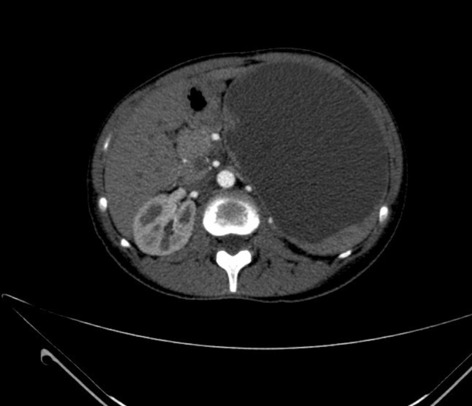

Methods: 3D virtual models were created through manual segmentation of CT and MRI scans obtained according to protocols routinely used in colorectal cancer staging. No extra patient time or preparation were needed. CT and MRI images were analysed by Gastrointestinal Radiologist to delineate the tumour and provide the cancer staging. Manual segmentation was then performed in 3D Slicer, an open-source, free software used for creation of three-dimensional anatomical models. Additional post-processing was applied in MeshLab or Blender.

Results: Ten 3D models depicting tumour deposits in colorectal cancer were created. Models of right- and left-sided bowel cancer with tumour deposits were derived from CT scans, while those of rectal cancer—from MRI scans. 3D models depicted bowel with the tumour and tumour deposits, relevant vasculature and lymph nodes, as well as surrounding structures as required. Models can be manipulated to allow for most comprehensible inspection of different anatomical structures and relationships. The transparency of each structure can be changed. The morphological appearance of tumour deposits and their relation to vessels can be readily appreciated. The morphological differences between the tumour deposits and lymph nodes, both benign and metastatic, can also be evaluated.